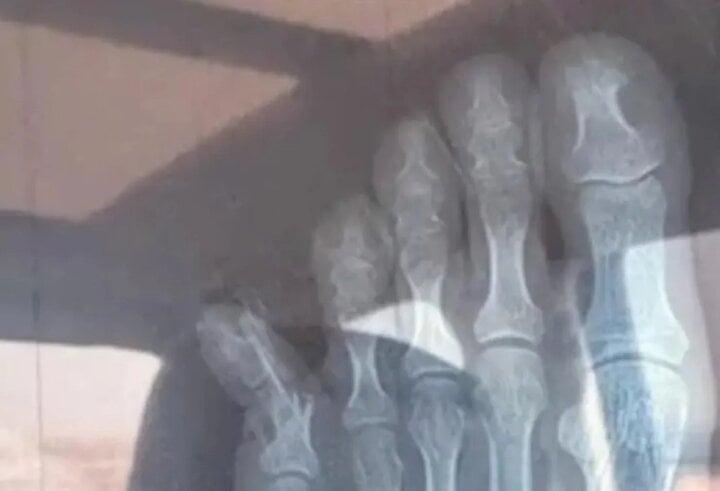

Ảnh chụp X-quang của Trương. (Ảnh: Baidu)

Kết quả chụp X-quang thể hiện rõ Trương bị gãy xương. Cô phải băng bó cả bàn chân. Sau khi sự việc xảy ra, Trương đăng ký cho con trai vào một lớp học thêm sau giờ học.

Hình ảnh được chia sẻ trên mạng cho thấy ngón chân út bên phải của Trương hướng hẳn ra ngoài, gần như tạo thành góc 45 độ.